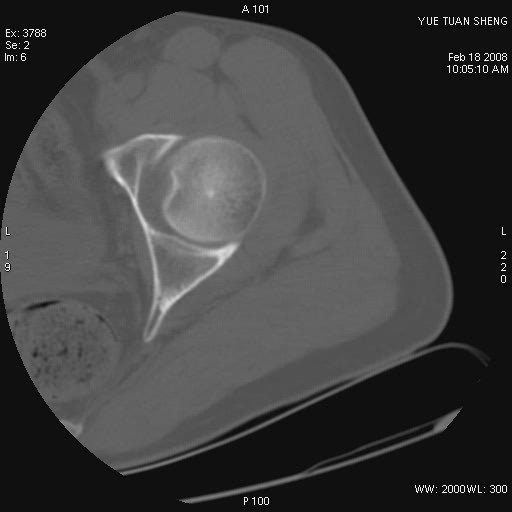

患者,男,56岁,左髋部疼痛1个月,x线:左股骨头高密度影,性质待定,右侧正常。左髋ct如图

左股骨颈区椭圆形磨玻璃样影,边缘明显硬化环环绕,其内见斑点状类钙化高密度影考虑 良性骨病-----骨纤,骨化性纤维瘤,内生软骨瘤。